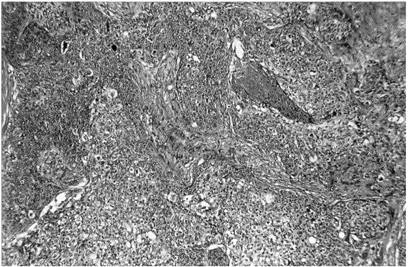

q carcinomul spinocelular include 10-15% dintre tumorile maligne ale pleoapelor si afecteaza mai frecvent pleoapa superioara si unghiul extern.

Clinic are un aspect vegetant, ulcerativ sau infiltrativ. Din punct de vedere evolutiv este mult mai agresiv decat carcinomul bazocelular, datorita caracterului invadant si metastazelor pe care le determina. Diagnosticul se pune pe examenul anatomopatologic (Fig. 7.9).